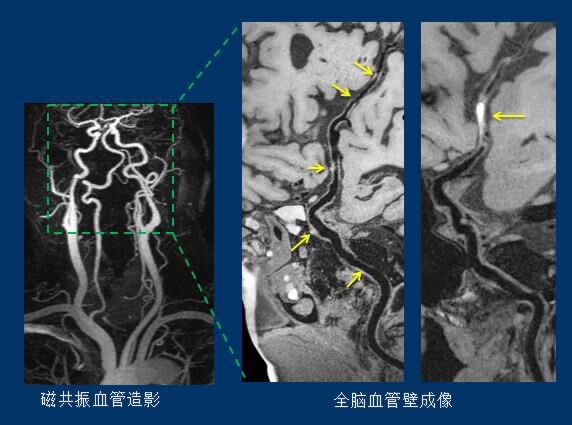

(左侧图像是现在医院里普遍使用的磁共振脑部血管造影的成像结果,图像反映的是脑动脉血管腔的形态。右侧两图像是血管壁成像技术下的图像,可以清楚显示脑动脉斑块和血栓。相同部位的图像,所包含的信息量不一样。)